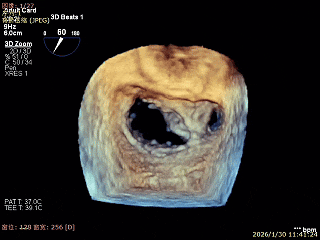

3D Enface 2区及3区前叶脱向左房

3D Enface 可见反流由2区3区从前后冲出

3D Enface下组织桥稳定无反流